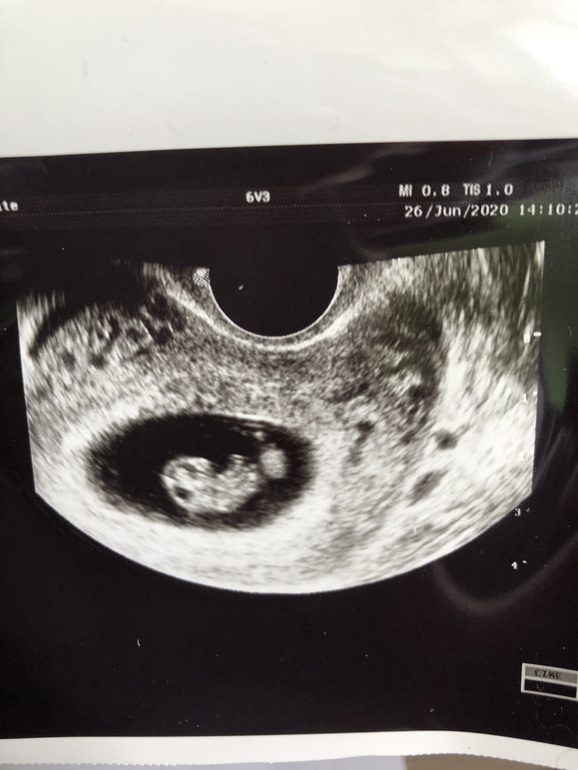

Мой головастик

У нас получилось! Я беременна!Сходила на узи и увидела свою малышку , сердечко бьется 💕и нас наконец выбрала она , спустя 1,5 года планирования и пролетных циклов , счастью нет предела 🙏🏼